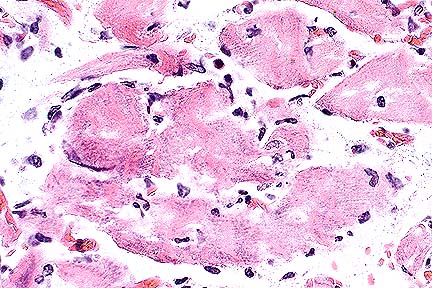

Post-surgical myofiber degeneration and necrosis in the hindlegs of a Percheron gelding. There is abundant amphophilic PAS-positive material within degenerate myocytes, suggesting a possible connection between exertional myopathy and a polysaccharide storage defect. (HE, 400X, 28K)

Slides submitted are either #5 (biceps femoris) or #9 (rectus femoris). On both slides, there is a transverse and a longitudinal section of skeletal muscle. On a few slides, the longitudinal section consists of only a few fibers with minimal lesion. On all transverse sections, and on available longitudinal sections, there is moderate to severe fiber size variation with increased numbers of internal nuclei. Myofibers are separated by a clear zone (edema, presumptive; possible autolysis). Numerous fibers contain pale to dark, amphophilic to basophilic, subsarcolemmal or internal loculated, aggregates of material that often replaces almost the entire diameter of the myofiber. Occasional fibers contain multiple clear cytoplasmic vacuoles. There is prominent segmental necrosis with macrophage infiltration of affected segments. Regenerating fiber segments are rare. There is mild (slide #9) to moderate (slide #5) patchy endomysial fibrosis and mild fatty infiltration (slide #5).

Periodic acid-Schiff (PAS) staining for glycogen reveals large granular aggregates of glycogen within many fibers and strong positive staining of the more organized aggregates visible on hematoxylin and eosin (H&E) stained sections. Following amylase digestion, the granular aggregates are largely amylase-sensitive, whereas the more organized aggregates are generally amylase-insensitive. Many macrophages contain PAS-positive material which is partially amylase-sensitive.

The case presented is a florid case with obvious storage material present on H&E stained sections. In other cases, this polysaccharide storage material is less obvious, and requires careful searching and PAS staining for diagnosis. In all cases, there are chronic myopathic changes, including excessive fibers size variation, type 2 fiber hypertrophy, presence of internal nuclei, and frequent separation of fibers by clear spaces thought to be edema. Muscles of the proximal hind limb are most severely and consistently affected. Amylase-insensitive polysaccharide material appears to increase with age.

AFIP Diagnosis: Skeletal muscle: Myofiber degeneration and necrosis, multifocal, moderate, with intramyocytic and intrahistiocytic granular amphophilic material, Percheron, equine.